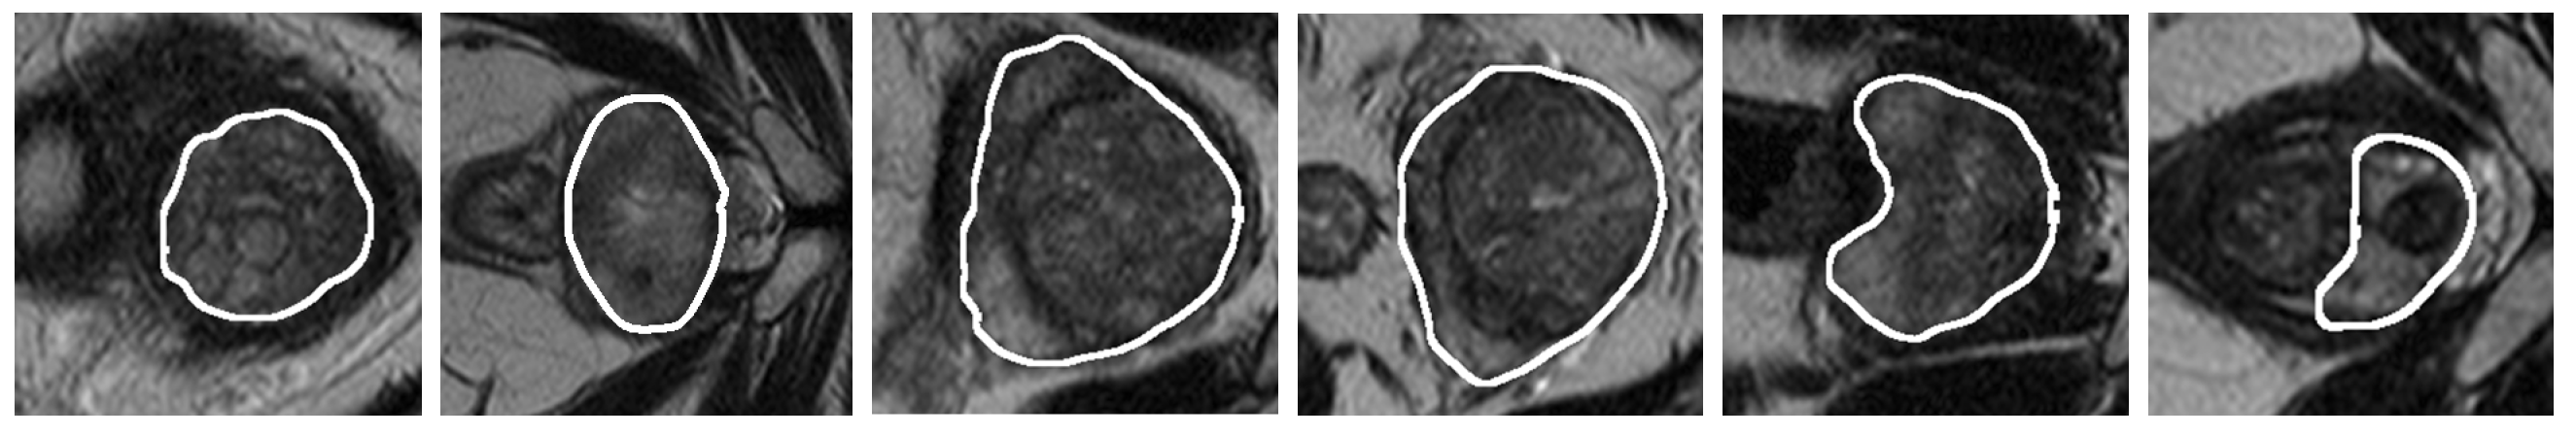

3. Validation of the Models